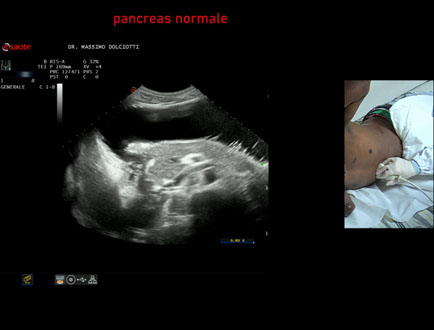

Data inserimento: 05/12/2024

Ecografia del: 28/11/2024

Strumento: Esaote MyLab Eight

Sonda: Convex Multifrequenza 1-8 MHz

Età Paziente: M 20 anni

Motivazione dell'esame: dolori addominali.

Commento all'esame: le immagini ed il video documentano il pancreas di ecostruttura e morfovolumetria regolare, con aspetto ipoecogeno, ben evidenziate la regione cefalica, il corpo e la coda.

Conclusioni: pancreas di ecostruttura e morfovolumetria regolare (pancreas with regular echostructure and morphovolumetry).

Presentazione: Dr. Massimo Dolciotti - Ancona

Elaborazione digitale: Andrea Dini - Ancona